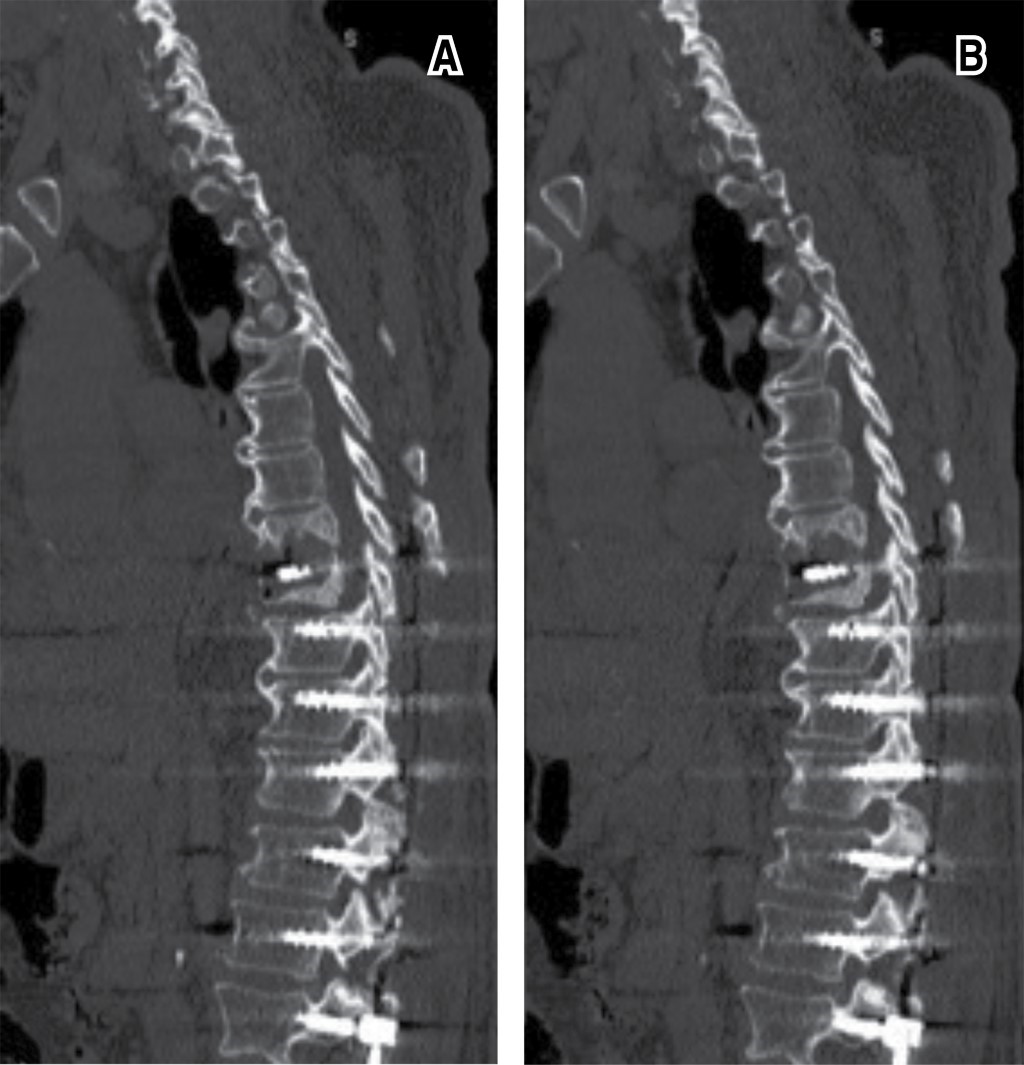

Paciente masculino con escoliosis lumbar degenerativa acompañado de enfermedad de Parkinson (EP). Se instrumenta únicamente los niveles necesarios para corrección de la deformidad coronal, como descompresión de los niveles con estenosis. A pesar de un control radiológico inmediato satisfactorio, en los días posteriores el paciente se aqueja de dolor a nivel de la columna torácica. Rayos X de seguimiento evidencian fractura de la vértebra más cefálica instrumentada. Debido a múltiples comorbilidades, se decide manejo conservador, esperando consolidación del segmento lesionado. Sin embargo, a pesar del tratamiento médico, es llevado cinco meses postoperatorio a sala de operaciones para prolongación de la instrumentación, realizando una transición de una fijación rígida a una semirrígida. El objetivo de la publicación es poner en contexto acerca de la dificultad que conlleva el manejo de un paciente que padezca EP combinado con algún padecimiento degenerativo de la columna.REFERENCIAS (EN ESTE ARTÍCULO)